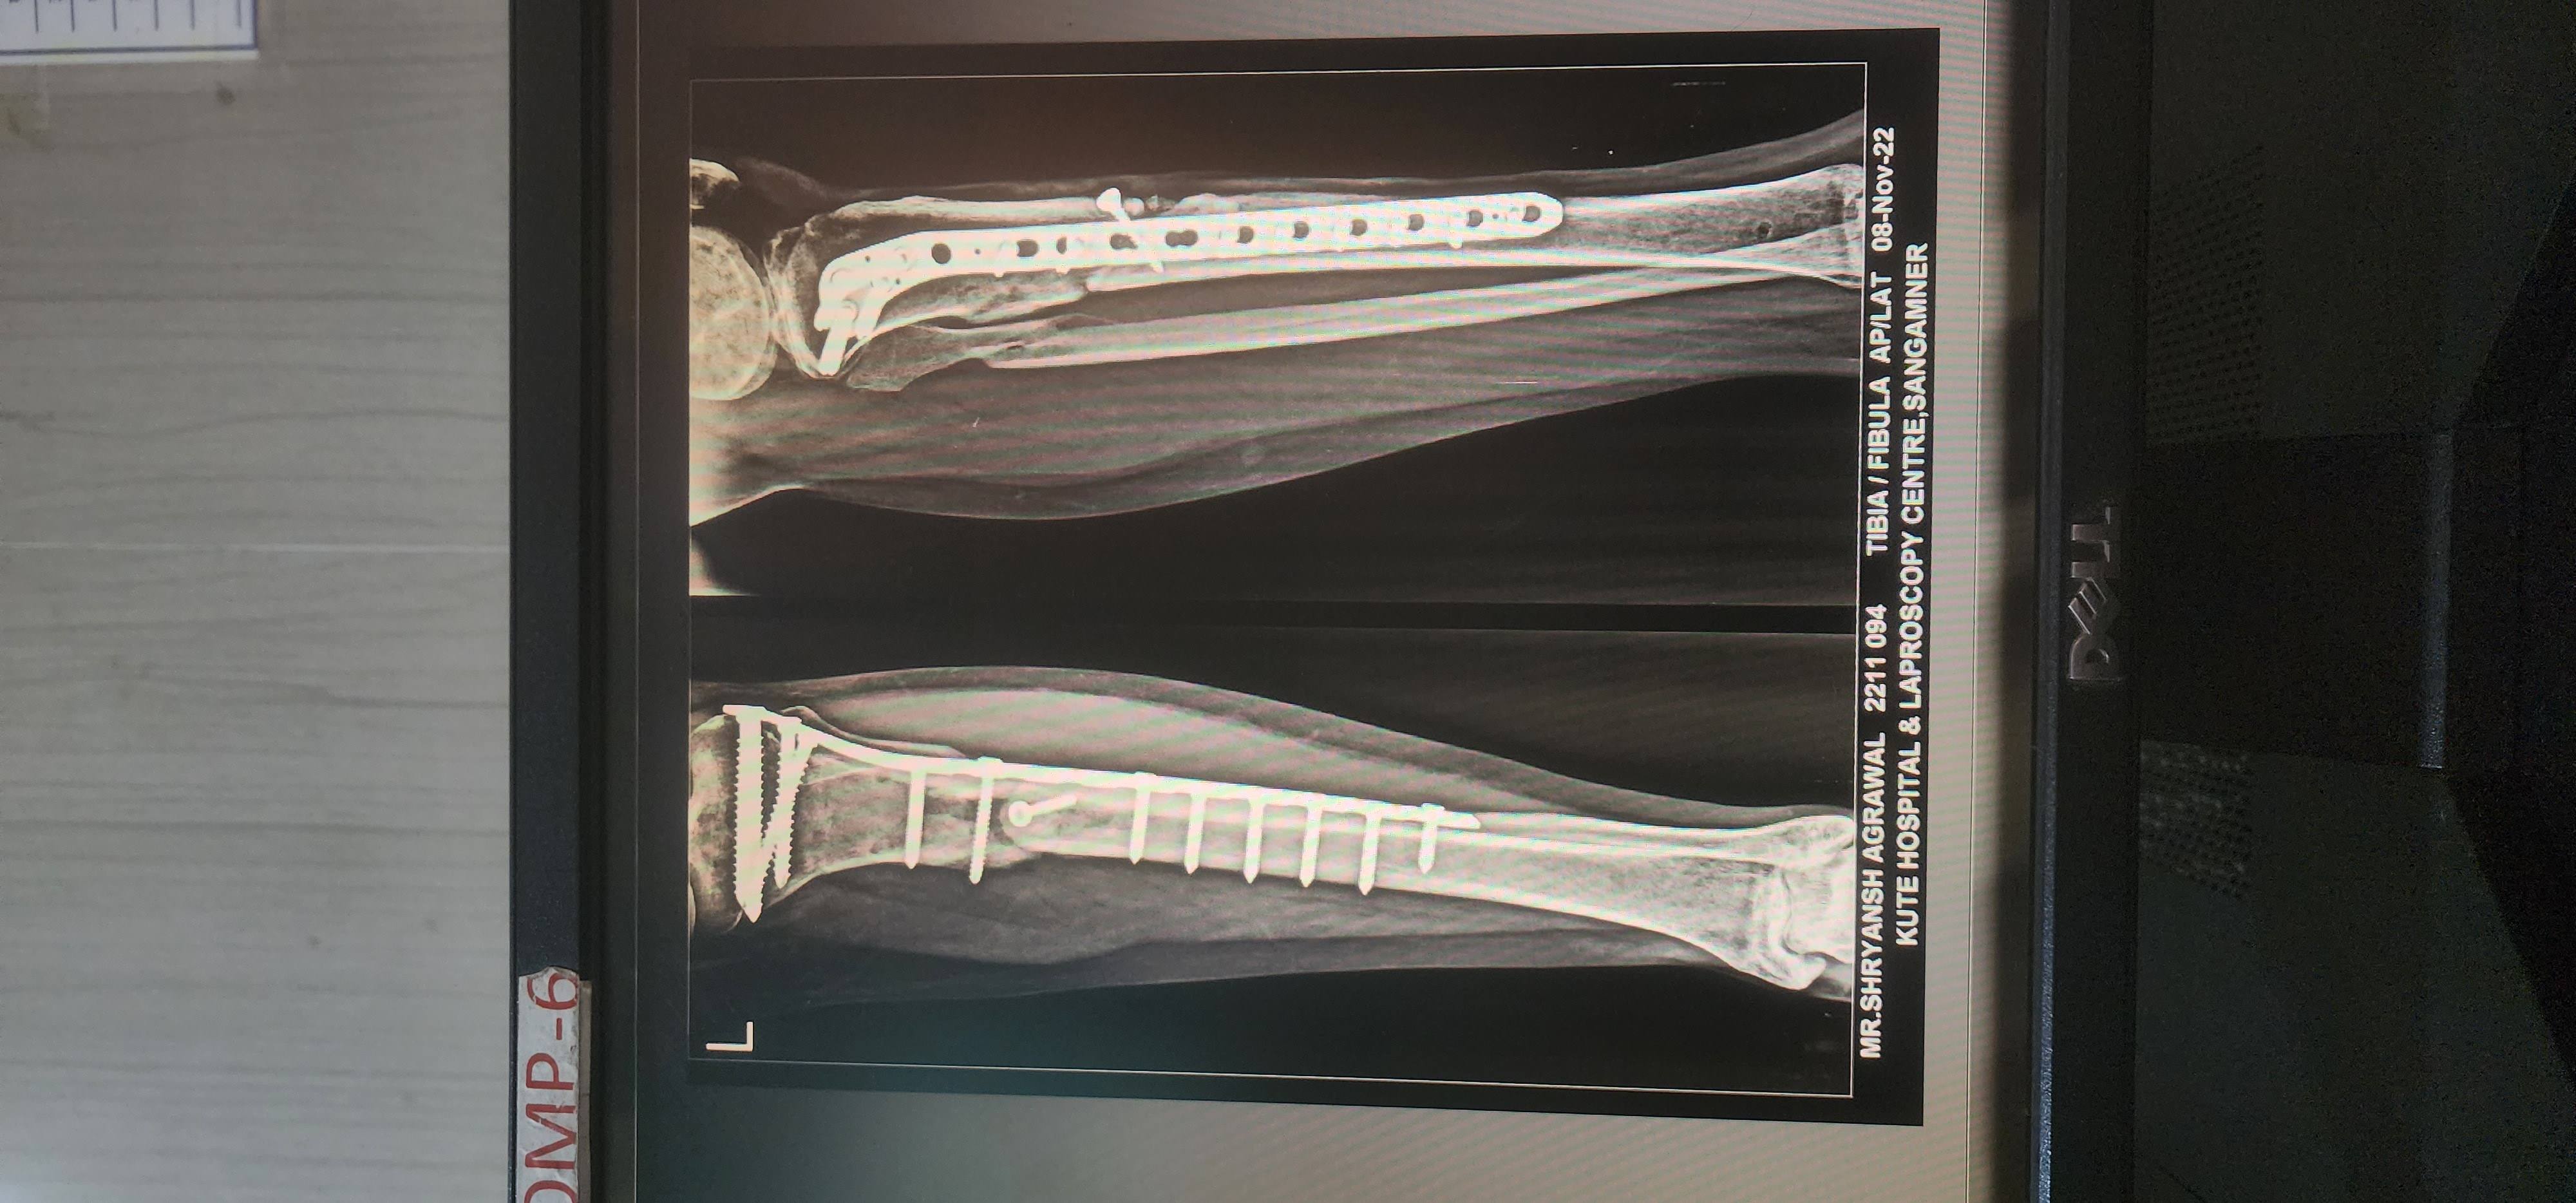

Sr accident 3Jan ko hua kacha plaster external rod skin grafting external rod nikala kacha plaster lgaya 15 apr ko internal rod lgaya 2machine baad uper vale 2screw me se 1uper vale screw pr phunsi jaisa ho gya sukta thik hota wapsse hojata complete solution btaye. Svastha jivan normal ho jaunga please reply sr